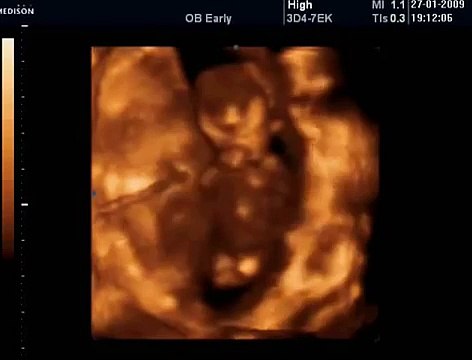

33 Haftalık Gebelik Bebek Ultrason Görüntüsü

Hafta hafta gebelik dönemi 33 haftalık bebek ultrason görüntüsü. Gebelikte 33. hafta daha çok bilgi için gebelikveannelik.com/33-hafta-gebelik sayfamızı ziyaret edebilirsiniz.